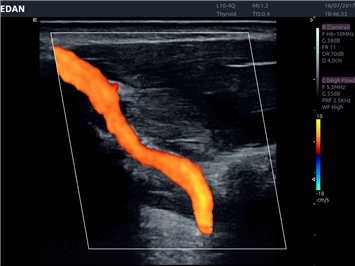

• Автоматическое измерение толщины интима-медиа

• Сосудистой диагностики

Цветовой допплер:

Да

Дуплексное сканирование: